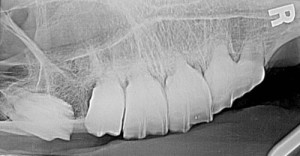

Digital x-ray equipment enhances our recognition and understanding of dental disease in the horse as it does in human and pet animal dentistry. Radiography in horses comes with its own challenges due to the size and thickness of the bones in the horse’s head. Yet, it is still the most useful tool to identify periodontal and pulp diseases. With digital equipment we can evaluate the tooth immediately and determine if a tooth is alive or dead. We can then make a therapeutic plan. Catching dental disease early can often help us save teeth that might otherwise need to be extracted. X-rays also are beneficial during and after tooth extraction to help determine what procedure may work the best and to be sure we have removed the entire tooth.